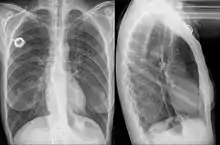

Esophageal stent

An esophageal stent is a stent (tube) placed in the esophagus to keep a blocked area open so the patient can swallow soft food and liquids. They are effective in the treatment of conditions causing intrinsic esophageal obstruction or external esophageal compression. For the palliative treatment of esophageal cancer most esophageal stents are self-expandable metallic stents. For benign esophageal disease such as refractory esophageal strictures, plastic stents are available. Common complications include chest pain, overgrowth of tissue around the stent and stent migration. Esophageal stents may also be used to staunch the bleeding of esophageal varices.[1]